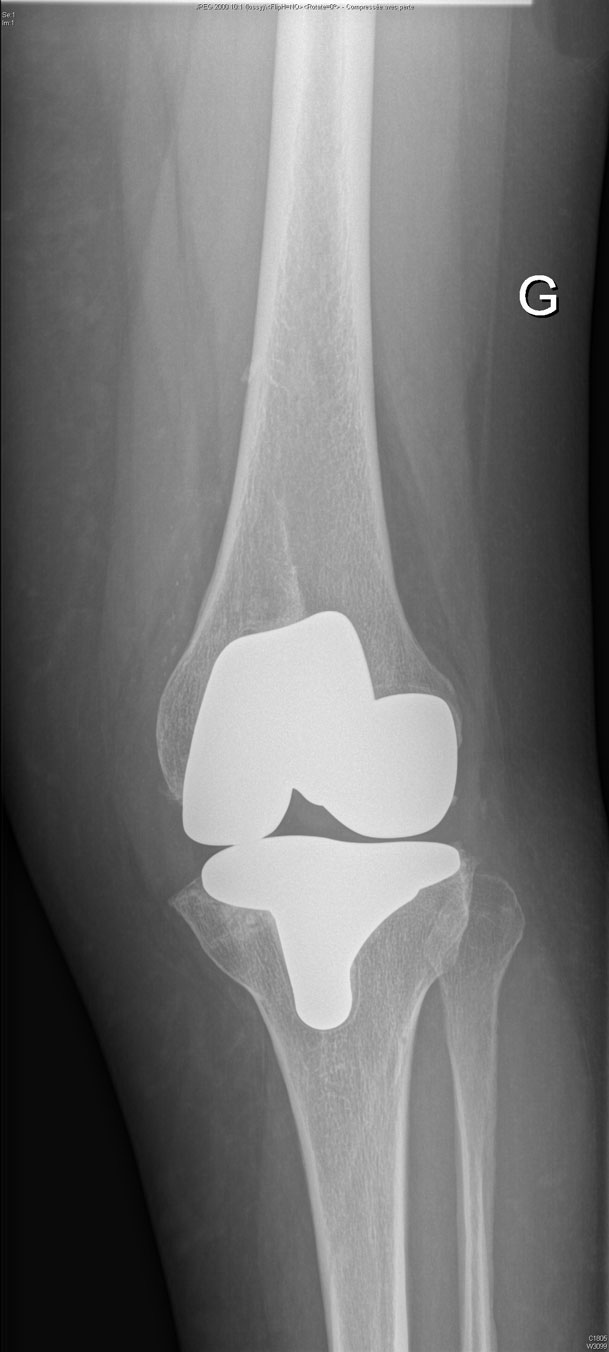

Reprise de prothèse totale du genou

La prothèse totale du genou est une entité complexe constituée de quatre éléments qui s'articulent ensemble lors des mouvements de flexion et d'extension de votre genou. Ces éléments sont :

L’implant fémoral

L’implant tibial

Le polyéthylène intermédiaire

L’implant rotulien

La planification préopératoire est une étape fondamentale au bon déroulement de votre intervention. Elle consiste à localiser précisément les zones de perte de substance osseuse, de dépister une laxité ligamentaire et de choisir les bons implants de reprise.